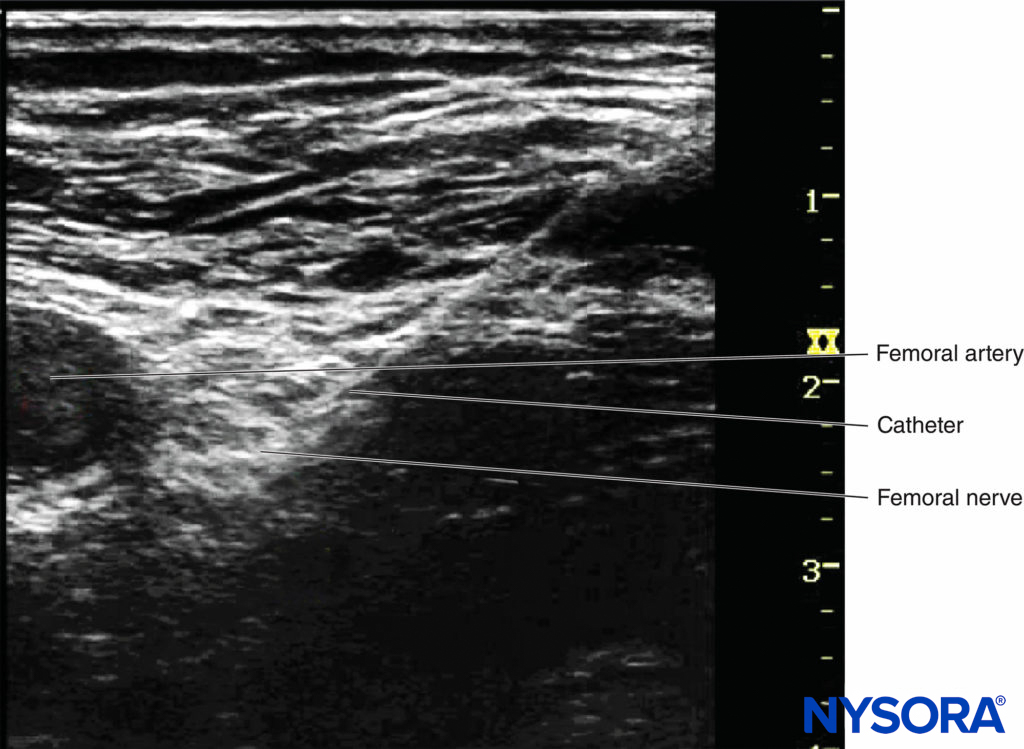

Continuous peripheral nerve blocks (CPNBs) have become a common practice; however, the visualization of the catheter tip can be challenging. Direct visualization of the catheter tip can be obtained when the catheter is introduced at a short distance from the needle tip (eg, 2 cm past the needle tip) (Figure 7).

However, when the catheter is inserted 3–5 cm past the needle tip, the needle, nerve, and catheter are never in the same plane of the ultrasound beam, therefore becoming challenging to image. There are two ways to confirm the catheter tip: (1) The operator can tilt or slightly slide the transducer to see a “bright dot,” which is the transverse view of the catheter. The position of the catheter tip can be detected by observing the spread of 1–2 mL injectate through the catheter, and the use of color Doppler may help visualize the spread more significantly (Figures 8A and 8B). (2) In some cases, the bright dot may not be obviously visualized or ensured; the operator has to slide the transducer within a certain distance away from the needle tip, with the distance based on the length of catheter threaded past the needle tip. Injection of 0.5 mL air can be beneficial to ascertain the position of the catheter tip with a sharp echoic contrast on the ultrasound image (Figures 9A and 9B). The obvious drawback is that injection of air may degrade the image for other purposes.

FIGURE 7. The catheter tip can be directly seen just beneath femoral nerve.

FIGURE 8. A: The position of catheter tip can be estimated by observing the spread of injectate. B: Doppler can be used to confirm the location of the spread.